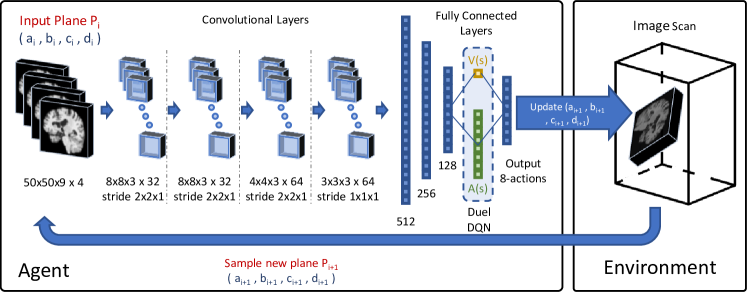

Multi-scale Agent: In order to provide more structural information, we introduce a novel multi-resolution approach in a coarse-to-fine fashion with hierarchical action steps. In this scenario, samples a grid of a fixed plane size of voxels around the plane origin and initial spacing mm. Initially, the agent searches for the plane with higher action steps. Once the target plane is found, samples the new planes with smaller spacing and the agent uses smaller action steps. Coarser levels in the hierarchy provide additional guidance to the optimization process by enabling the agent to see larger context of the image. Whereas, finer scales provide sharper adjustments for the final estimation of the plane. Similarly, larger step actions speed up the solution towards the target plane, while smaller steps fine tune the final estimation of plane parameters. The same DQN is shared between all levels in the hierarchy, see Fig. 1. The next section exhibits results of utilizing this multi-scale approach.

Implementation Training times are around hours for the brain experiments and days for the cardiac experiments using an NVIDIA GTX 1080Ti GPU. During inference, the agent finds the target plane using iterative steps, where each step takes s. The details of the our proposed network for DQN are in Figure 1. The source code of our implementation is publicly available on github https://git.io/vhuMZ.